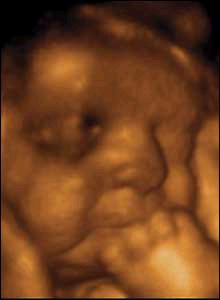

- Fóstrið mælist nú 16 sm og vegur tæplega 300 gr.

- Nú er góður tími til að fara í sónar. Þá er meðgöngulengdin metin, hvar fylgjan er staðsett, legvatnsmagnið er metið og hugsanlegir fósturgallar greindir.

- Nú er fóstrið orðið það stórt að auðveldara er að skoða einstök líffæri og líffærakerfi

- Meðgöngulengd er reiknuð út frá stærð höfuðsins og lengd lærleggjarins

Fjölburaþunganir greinast ef ekki hefur verið ómskoðað áður. - Staðsetning fylgju er skoðuð

- Hingað til hefur lifur og milta fóstursins framleitt blóðfrumur. Nú tekur beinmergurinn til starfa og smátt og smátt yfirtekur hann alveg þetta hlutverk. Lifrin hættir framleiðslu blóðfruma nokkrum vikum fyrir fæðingu og miltað hættir framleiðslu í kringum 30. viku meðgöngunnar.

- Í lok þessarar viku er meðgangan u.þ.b. hálfnuð